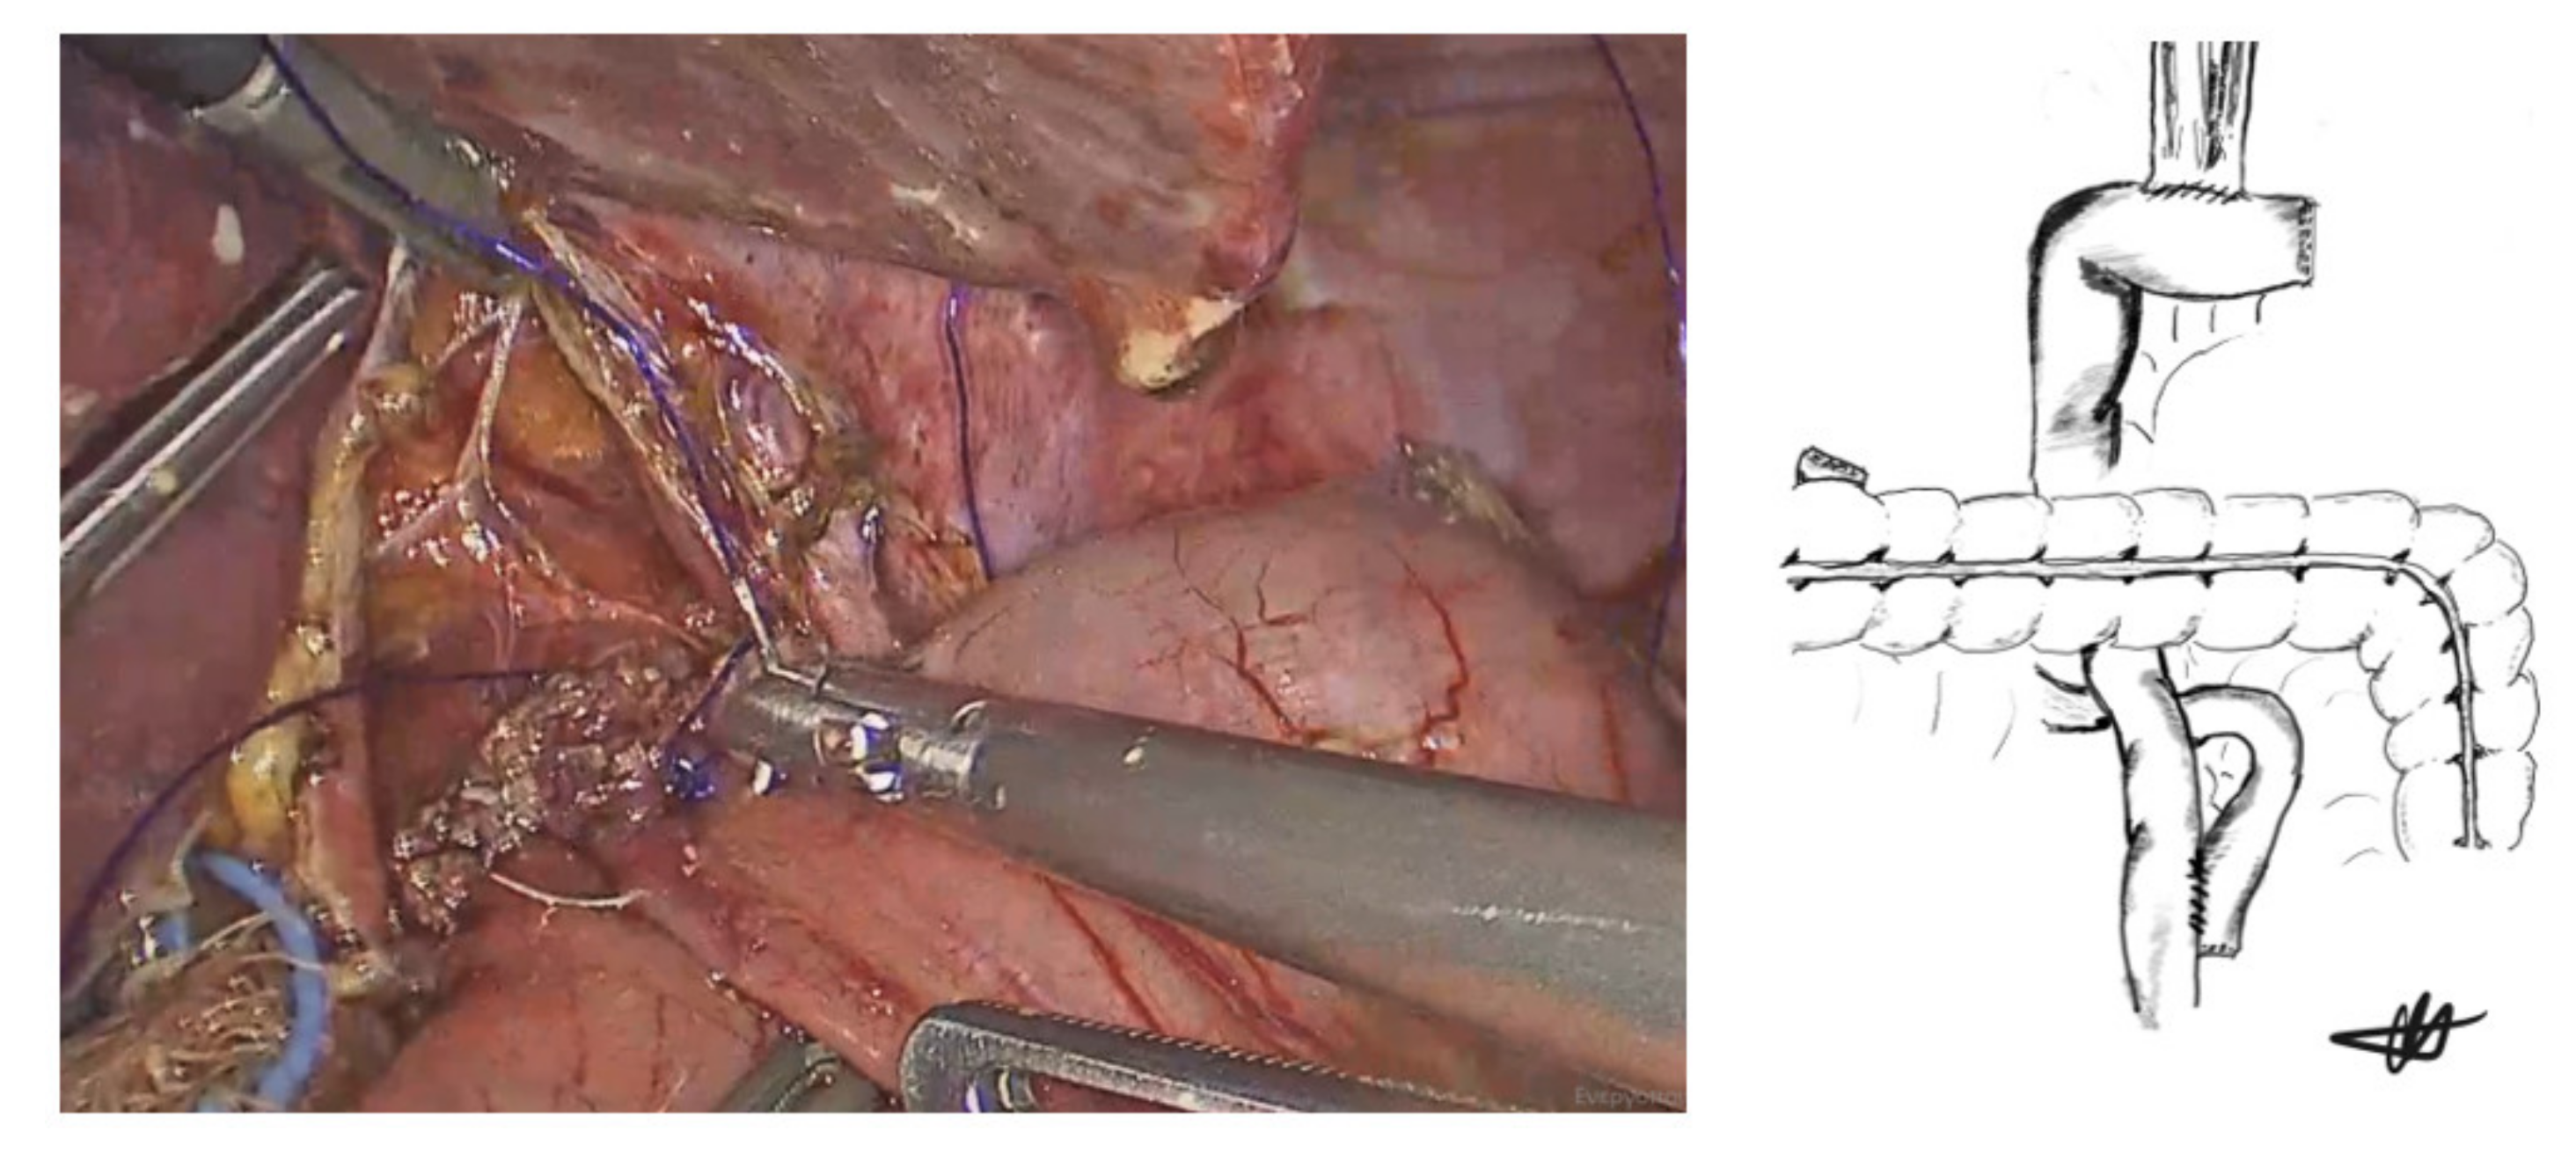

2.2. Laparoscopic Hand-Sewn Esophago-Jejunal Anastomosis